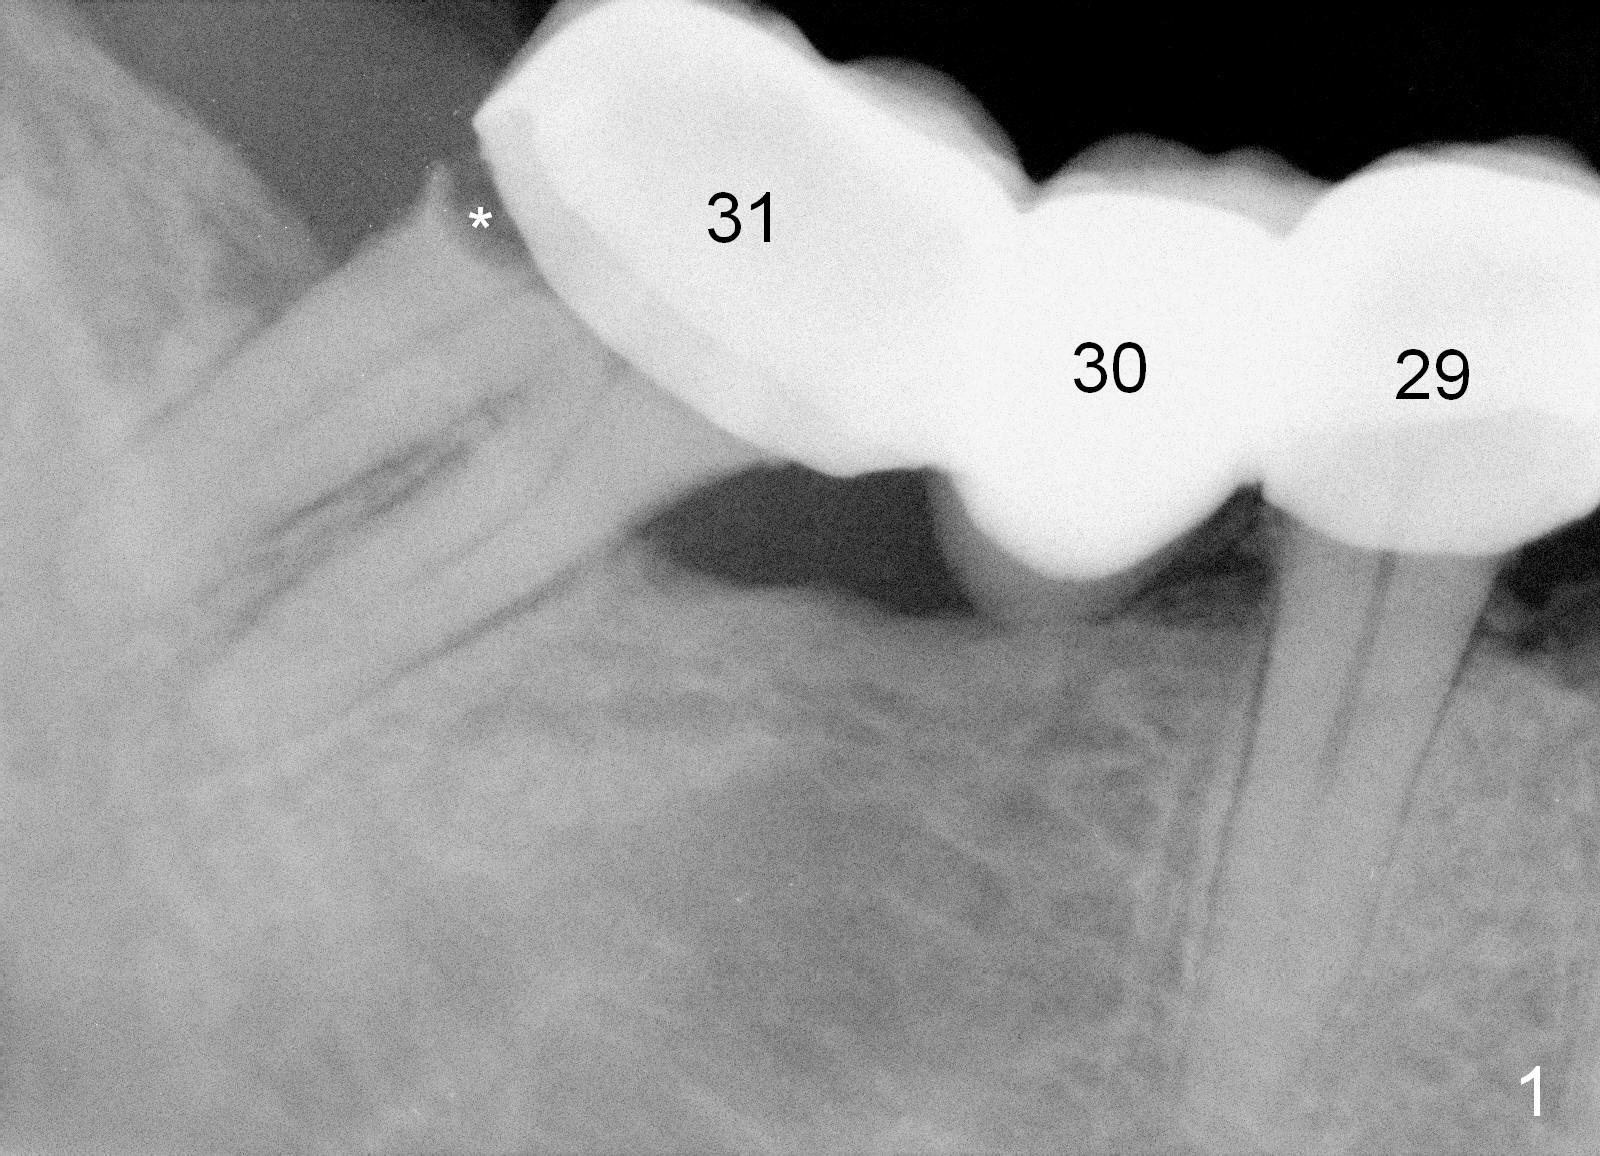

A 43-year-old man has a failed bridge (Fig.1: #29-31). The mesiodistal width of the pontic (#30) is pathologically narrow. When an implant is placed at the site, the osteotomy position should be moved distally, 5 mm from the distal surface of the tooth #29 (Fig.3), while the center of the osteotomy at the site of #31 should be 10 mm from the center of the osteotomy at the 1st molar.

Therefore, it is safer to place an implant coronal to the white arrowheads, i.e., 2 mm apical to the apex of the mesial socket (compare Fig.2,3).

The length of tissue-level implants should be confined to 14 mm (Fig.4).